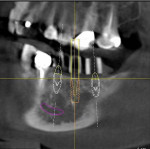

A cone-beam x-ray was taken, and the location of the mandibular nerve was mapped out (Galileos, Sirona Dental Systems). The long axis of the planned implant positions, represented by the long axis of the guide sleeve images, was evaluated in the mesio-distal and bucco-lingual planes for each site. Using the Galileos software, three virtual implants were superimposed on the x-rays to determine the appropriate size and positions for each of the three implants (Figure 4, FIgure 5, Figure 6, Figure 7, Figure 8 and Figure 9).

The treatment plan was to place three implants above the mandibular nerve without grafting or augmenting the alveolar ridge, using one implant to support each of the three missing teeth. The long axis of the diagnostic cylinders—indicating the long axis of the planned osteotomies—and the long axis of the virtual implants were determined in both the mesio-distal and bucco-lingual plane. A line was drawn through the center of the image of the diagnostic cylinders and the long axis of the virtual implants.

Analyze and Correct

In this case, the long axes of each of the three guide sleeves were analyzed in the bucco-lingual and mesio-distal planes in the cone-beam images (see Figure 4 through Figure 9), and the following corrections were made. The guide sleeve for the second bicuspid was corrected by bending the guidepost 12º in a mesio-distal plane and 15º toward the lingual in the bucco-lingual plane (see Figure 4 and Figure 5). The guidepost in the first molar position was corrected 33º to the lingual (see Figure 6 and Figure 7), and the guidepost for the second molar was corrected by bending it 30º to the lingual (see Figure 8 and Figure 9).